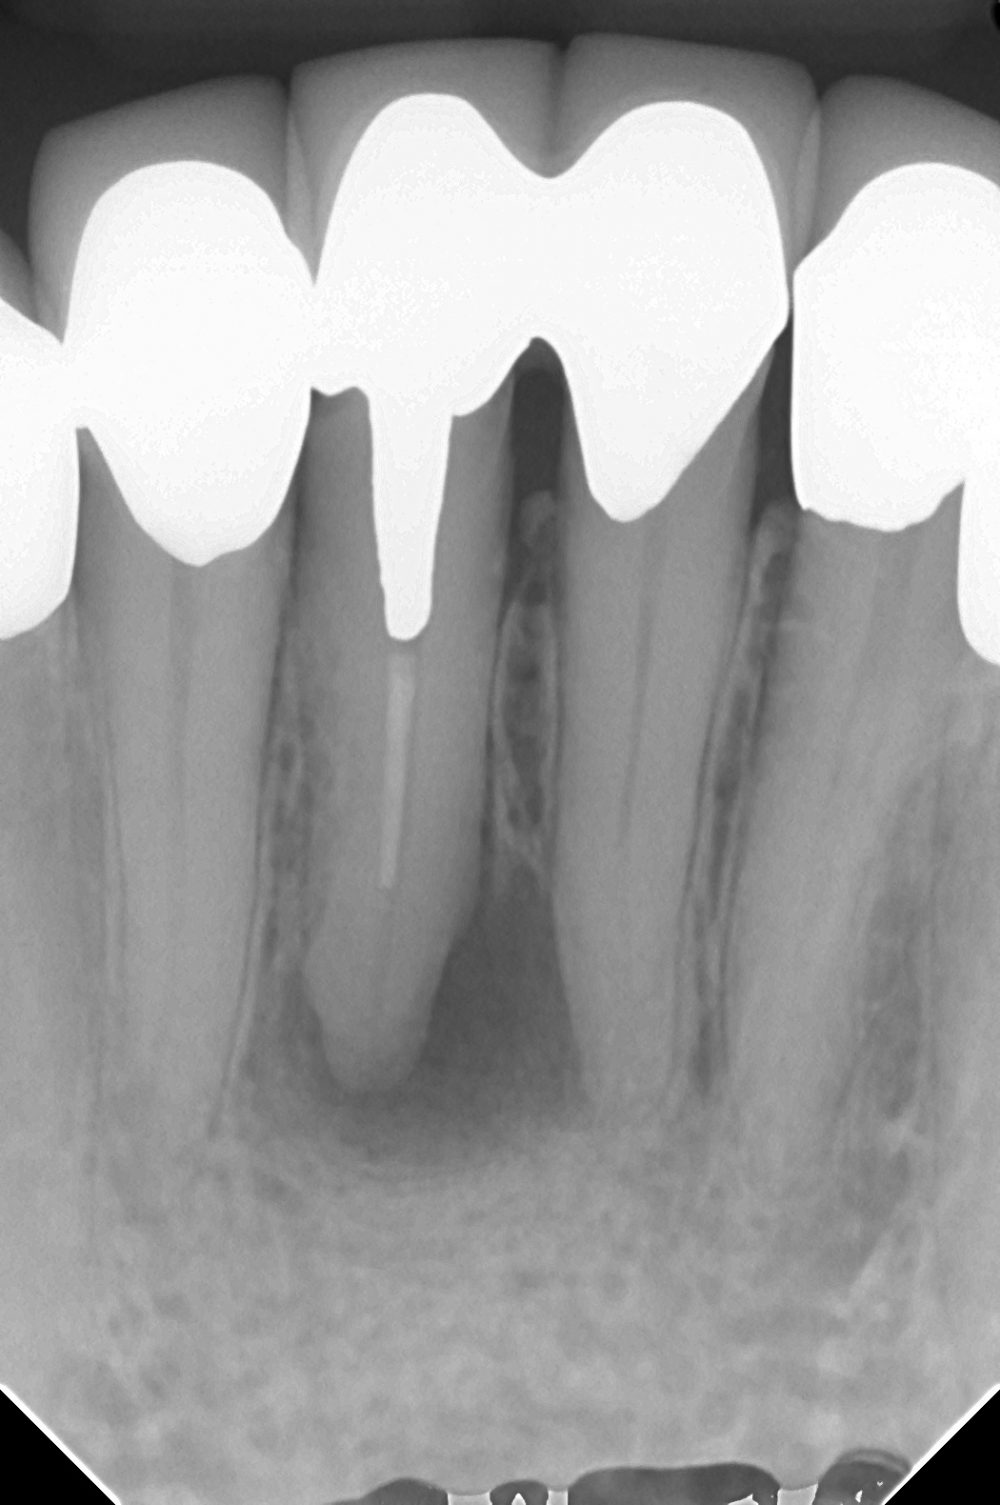

さて、今回のケースです。

歯内療法医が嫌がる、下顎前歯です。

骨の透過像の配列がサークル上になっているのが解りますでしょうか?

ひょっとしたらアクチノマイセスに感染しているのかもしれないとか考えつつ治療を始めます。

白い線はラバーダムフレームです。